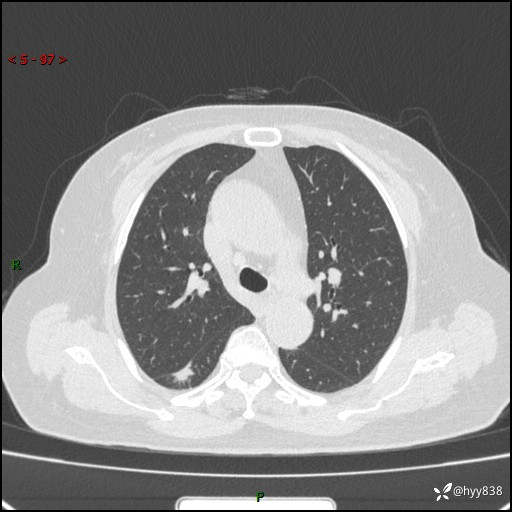

71岁/女,发现肺结节1月。偶然发现孤立肺结节,邻近叶间裂凹陷---结果公布(再回首)

【患者信息】:71岁/女

【主诉】:发现肺结节1月

【现病史及既往史】:2024年9月患者因“胆囊结石”于我院肝胆外科住院,期间完善胸部CT提示:右下肺结节灶,高危结节?感染?,病程中无畏寒发热,无咳嗽、咳痰,无活动后气短,无心慌胸闷,无胸痛、咯血,无头晕头痛,无腹痛腹泻,无四肢肌肉酸痛等不适,当时建议其择期复查。今日患者为求进一步复查就诊于我院,完善胸部CT提示:右肺结节,较前一致,遂门诊“肺部结节”收入我科。 自本次起病以来,患者精神、饮食、睡眠可,大小便正常,体力、体重未见明显异常。

【检查】:胸部CT平扫+增强